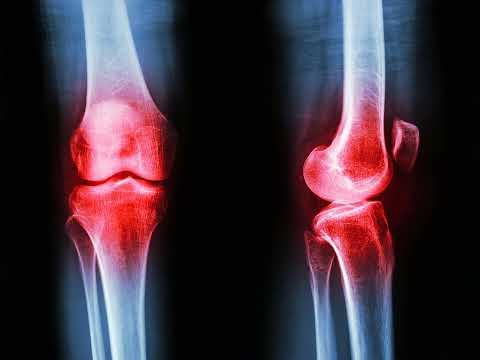

Артрит — це широкий термін, що охоплює різні стани: від дегенеративного остеоартриту до аутоімунних захворювань, таких як ревматоїдний артрит. Незважаючи на відмінності в походженні, у всіх цих станів є спільний ворог: хронічне запалення, яке призводить до болю, скутості та втрати рухливості.

Це створює потенційний «подвійний ефект» для пацієнтів. Нині зниження ваги є стандартною рекомендацією для пацієнтів із артритом, оскільки зменшення маси тіла знижує механічне навантаження на суглоби. Нове дослідження передбачає, що препарати GLP-1 можуть дати вторинну перевагу: високі рівні гормону, що циркулюють у крові, можуть проникати у тканини суглобів та безпосередньо впливати на запалення.